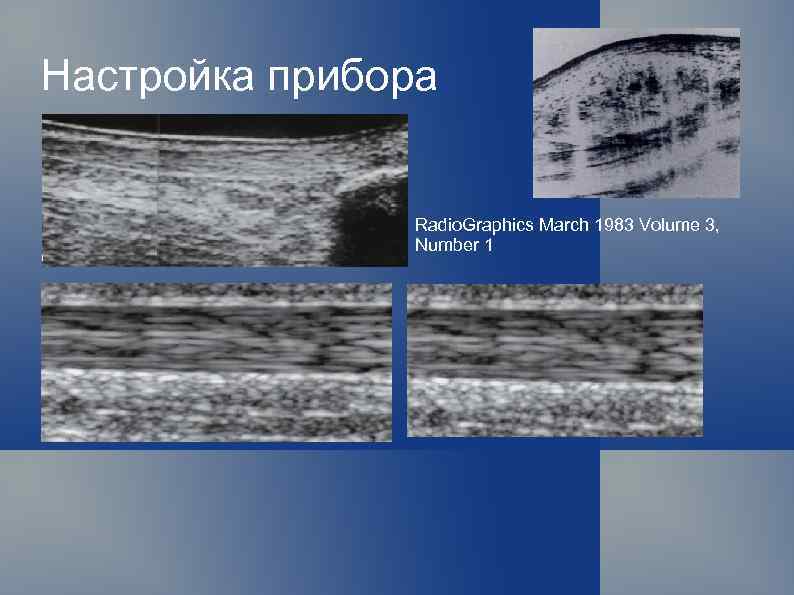

Настройка прибора Radio. Graphics Мarch 1983 Volume 3, Number 1